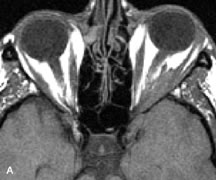

Metastatic Tumors

Breast carcinoma metastatic to the orbit has been demonstrated to be hypointense to the surrounding orbital fat on T1-weighted studies and hyperintense on T2-weighted images and has an affinity to the extraocular muscles (Fig. 20).50,64 The MRI characteristics of prostate carcinoma metastatic to the orbit have been described as involving the greater and lesser wing of the sphenoid, orbital roof, and optic canal. Diffuse bone hypertrophy with isointense or slightly hyperintense tissue on T1-weighted images represents the osteoblastic carcinomatous bone infiltration. Contrast enhancement is variable on T1-weighted and fat-suppressed images.65

Fig. 20. A. T1-weighted MR scan demonstrates nodular enlargement of both medial rectus muscles (arrows). B. T1-weighted fat-suppressed contrast-enhanced scan confirms the presence of small metnstatic deposits within the muscles (open arrows).